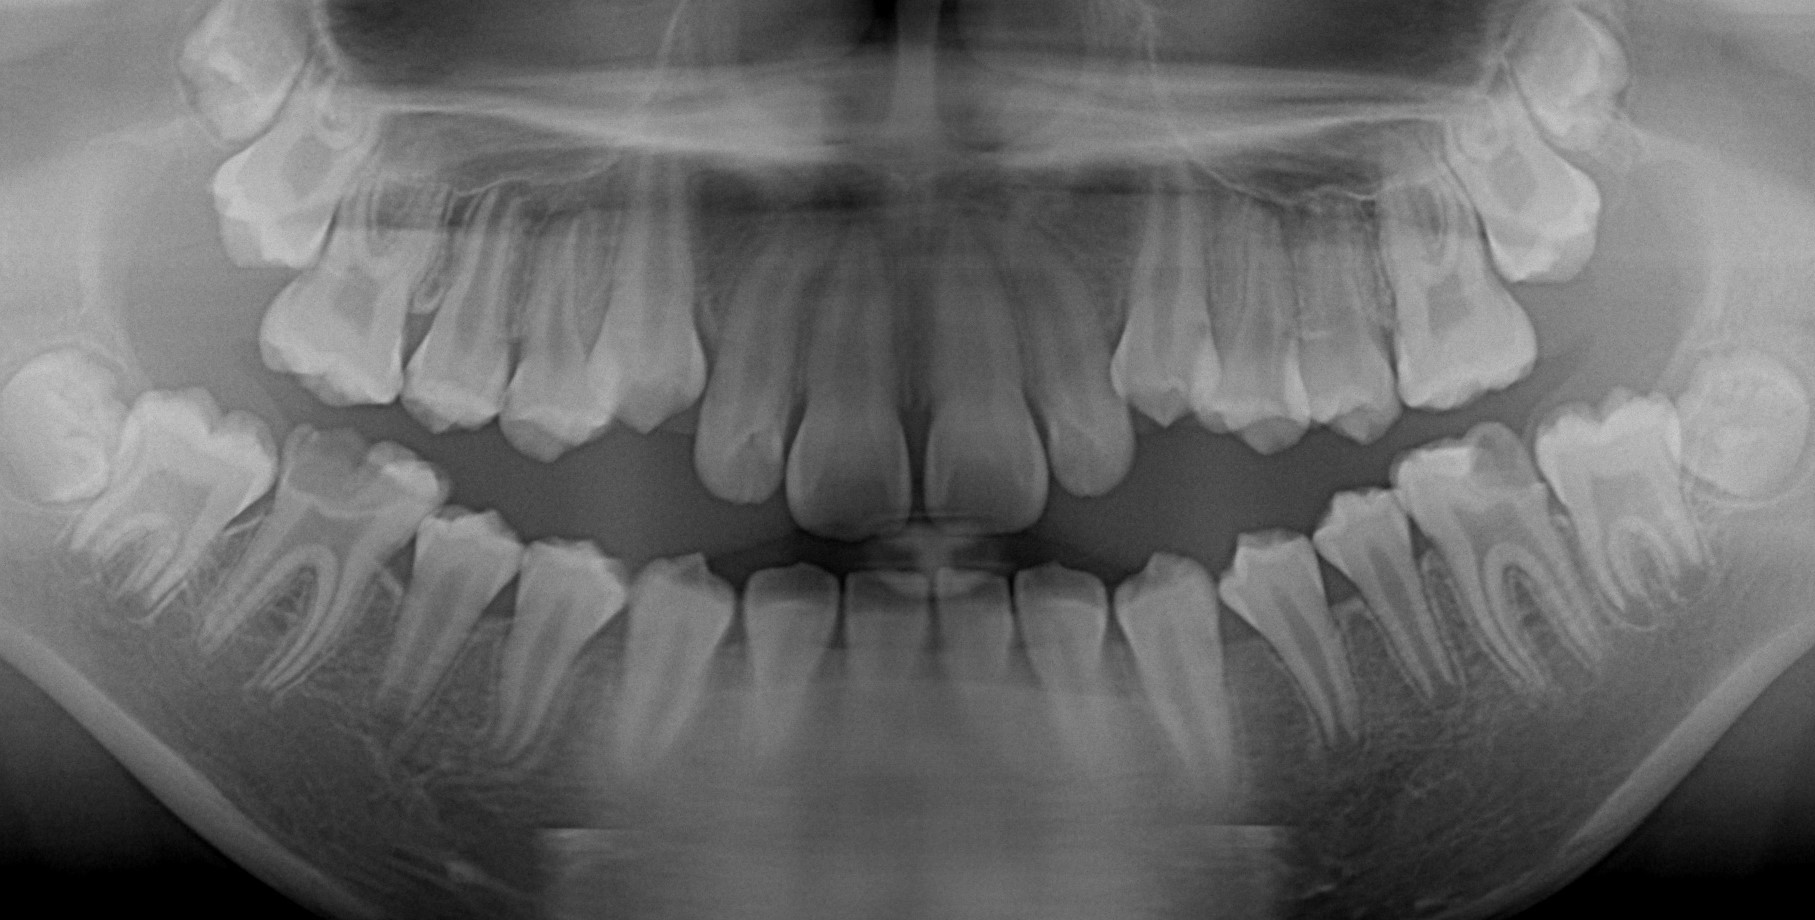

実際の症例

治療前です 下の奥歯が著しく崩壊しています

本来なら神経を取る治療を行うと思いますが、ドックスセメントにて神経の保護をはかりました